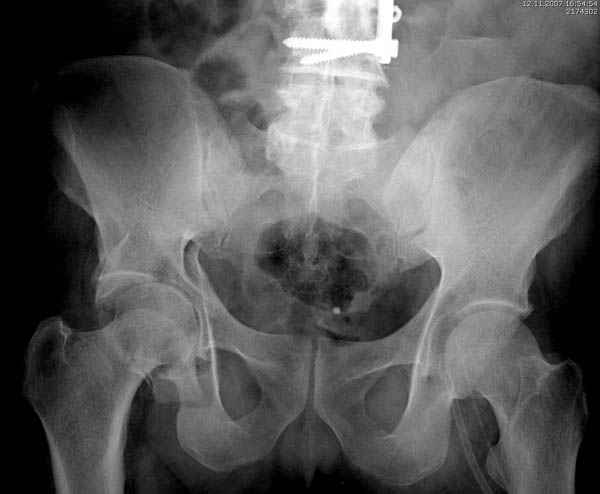

Прооперирован вчера на 13 день после поступления.

Больному 41 и из-за гемодинамической нестабильности в течение первых 7 дней был в реанимации под интубационной седацией.

Кроме перелома плеча у больного старый дистракционный перелом T12-L1 оперированный когда-то и кем-то, открытый перелом костей предплечья, который был прооперирован в ночь поступления, после I&D (хирургической обработки). Из-за разрыва селезенки при поступлении травма хирургами произведено удаление.

Дополнительно имеется перелом ацетабулума: задняя

колонна с полупоперечным переломом, и переломы костей лица.

На седьмой день зафиксирован перелом ацетабулума через задний доступ. Перед операцией для профилактики DVT, IVC фильтер, также получает Lovenox.

Извиняюсь за качества снимков, обычный больной в 300 фунтов, портативным ренген аппаратом не пробить.